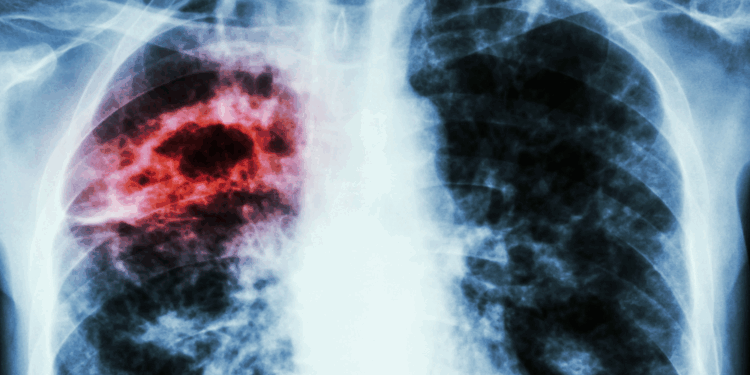

México.- Ante el creciente impacto del cáncer de pulmón, el más letal del mundo, el director médico de Amgen México, Max Saráchaga, hizo un llamado este jueves a las personas con factores de riesgo a no postergar las revisiones médicas y acudir a chequeos que permitan una detección temprana.

Asimismo, la compañía destacó que una de las razones de su alta letalidad es que la mayoría de los casos se diagnostican en etapas avanzadas, cuando los síntomas -como tos persistente, dolor torácico o falta de aire- ya están presentes y las opciones de tratamiento son limitadas.